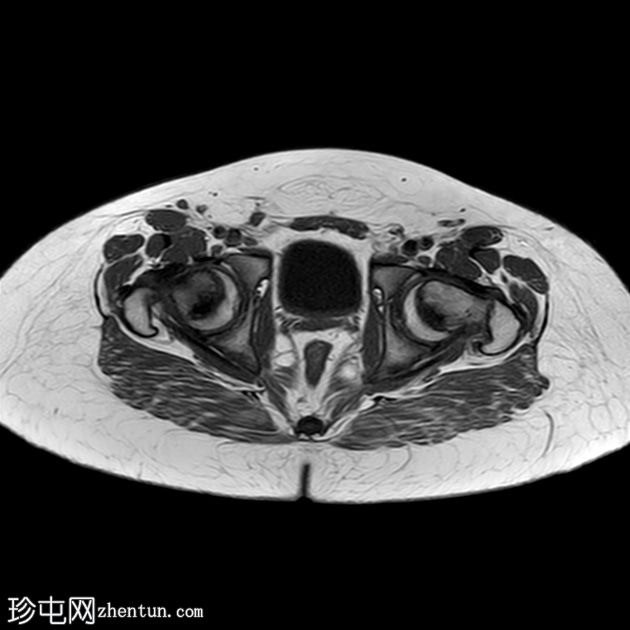

轴位片

T1加权像

双侧股骨近端骨骺皮质不规则,轻度增宽,伴股骨骨骺及近端干骺端骨髓水肿。

双侧股骨骨骺轻度后内侧移位。

双侧轻度髋关节积液。

双侧轻度股骨头骨骺滑脱(SCFE)属于Salter-Harris I型骨折,由于没有正常侧可供比较,因此在X线片上容易被漏诊。

之所以称之为轻度,是因为骨骺外侧缘仍位于干骺端外侧三分之一处。